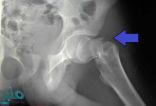

مجموعة عوامل خطرة ترفع أحتمالات كسر الفخذ

من الممكن أن يكون التعرض لكسر عظمة الفخذ أمرا مهما وذا تأثيرات صحية خطيرة، ومَن يصابوا بكسر عظمة الفخذ هم عرضة بنسبة 18 في المائة للوفاة خلال عام من حصول ..